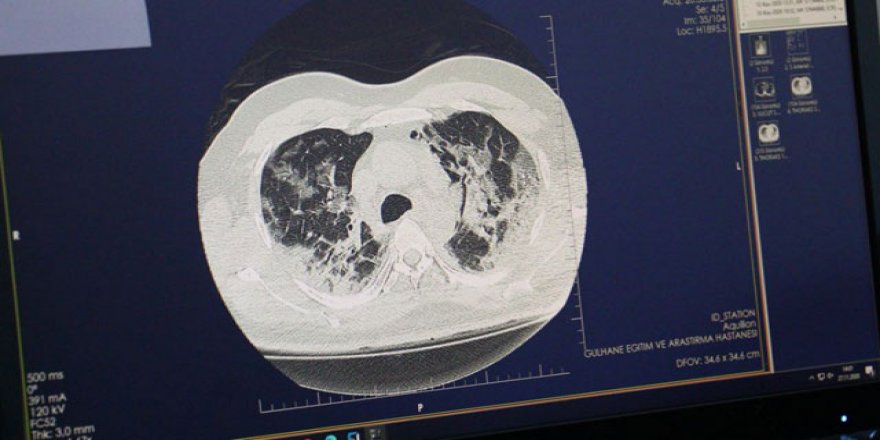

Covid-19'un akciğerdeki hasarı, tomografi görüntülerinde

Ankara Sağlık Bilimleri Üniversitesi Gülhane Eğitim ve Araştırma Hastanesi Göğüs Hastalıkları Uzmanı Doç. Dr. Cantürk Taşçı, hastalara ait tomografi görüntüleri üzerinden Covid-19'un akciğerde yarattığı tahribatı anlattı.

Sağlık Bilimleri Üniversitesi Gülhane Eğitim ve Araştırma Hastanesi'nde Covid-19 tedavisi gören hastaların akciğerlerindeki tahribat, tomografi görüntülerine yansıdı. Görüntülerde, hastalığın ne kadar hızlı ilerlediği, akciğeri nasıl tuttuğu ve yarattığı hasar gözler önüne serildi. Göğüs Hastalıkları Uzmanı Doç. Dr. Cantürk Taşçı, Covid-19'un akciğere girişini ve bıraktığı hasarı anlattı. Prof. Dr. Taşçı, "Koronavirüs ağız ve burundan akciğerlerimize ulaşabilmekte, tek giriş yolu burası. Tabii her hastamızda akciğere ulaşım olmuyor. İmmün sistemi sağlam olan kişilerde, daha çok gençlerde bu virüs üst solunum yollarında kalabiliyor. Bunlarda daha çok kısmi semptomlarla, hatta aseptomatik olarak seyredebiliyor. Akciğerde tutulma olmadan gribal semptomlar ile bu hastalığı atlatabiliyorlar" dedi.

Doç. Dr. Taşçı, koronavirüsün akciğerdeki solunum keseciklerinde hasara yol açtığını kaydederek, "Orada bir sertleşme, büzüşme, solunum keseciklerinin fonksiyonlarını yitirmesine neden oluyor. Bu, yaygınlığı, şiddeti arttıkça hastaları solunum yetmezliğine götürebiliyor. Ama dediğim gibi her hastada farklı seyretmekte. Hastanın kendi bağışıklık sisteminin gücüyle beraber bazı hastalarda solunum yetmezliğine, bir kısım hastada yoğun bakıma kadar ilerleyebilmekte. Bazı hastalarda çok yaygın akciğer büzüşmesi denilen tabloya yol açıyor. Tabii ki bu hastaları biz yine iyileştiklerinde taburcu ediyoruz; ama akciğerdeki düzelmeler akciğer büzüşmesi oluştuysa ayları bulabiliyor. Onun dışında o kadar şiddetli değilse taburcu olduktan yaklaşık 1 hafta 10 gün sonra akciğerleri tamamen normale de dönebiliyor. Akciğerde kalıcı hasar şu ana kadar gördüklerimizde yok. Hastaları kontrollere çağırıyoruz, akciğer hasarı takiplerimizde hemen hemen yok" ifadelerini kullandı.